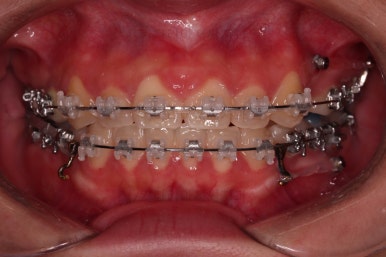

초진 시 입안의 모습을 보실게요.

결국은 앞니 사이에 틈이 생겼기 때문에 이같은 문제점을 인지하시고 내원하셨던거죠.

환자분 : "임플란트 하기 전에 앞니 틈도 모으고 싶어요."

키다리 : "임플란트 안하고 마무리를 해보실래요?"

환자분 : "네??"

치아가 없다고 모든 경우 임플란트를 치아가 없는 갯수만큼 해야 되는 건 아닙니다.

이번 환자분의 경우는 치아 결손 부위의 잇몸뼈도 양호했고 공간도 그리 크진 않았으며 윗니는 갯수가 1개 부족해도 교합을 맞추는데 문제가 거의 없기 때문에 시간이 좀 더 들더라도 임플란트 없이 앞니 사이 틈과 결손부위 틈새를 모아보기로 했어요.